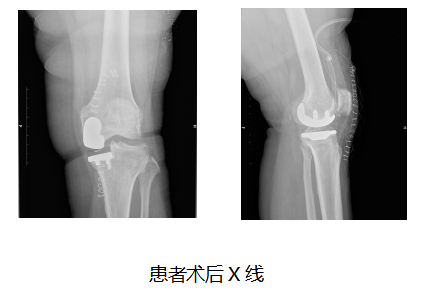

結合術前檢查及AI規劃,宋科官教授決定採用固定平臺單髁系統。宋科官教授介紹,固定平臺單髁系統區分左右側的解剖式設計,更貼合骨面,固定平臺襯墊脫位風險低,XLK高交聯聚乙烯材質配合高拋光脛骨平臺有效降低了假體的磨損,也提高了假體生存率。

經過術前詳盡的規劃預演,董阿姨的手術非常順利,手術僅花費一個小時便成功完成。術中實際與術前規劃一致,術後患者感覺疼痛明顯減輕,第二天便下地行走。董阿姨出院時念叨“早知道這麼容易就能治好,真是白忍了這五年”。